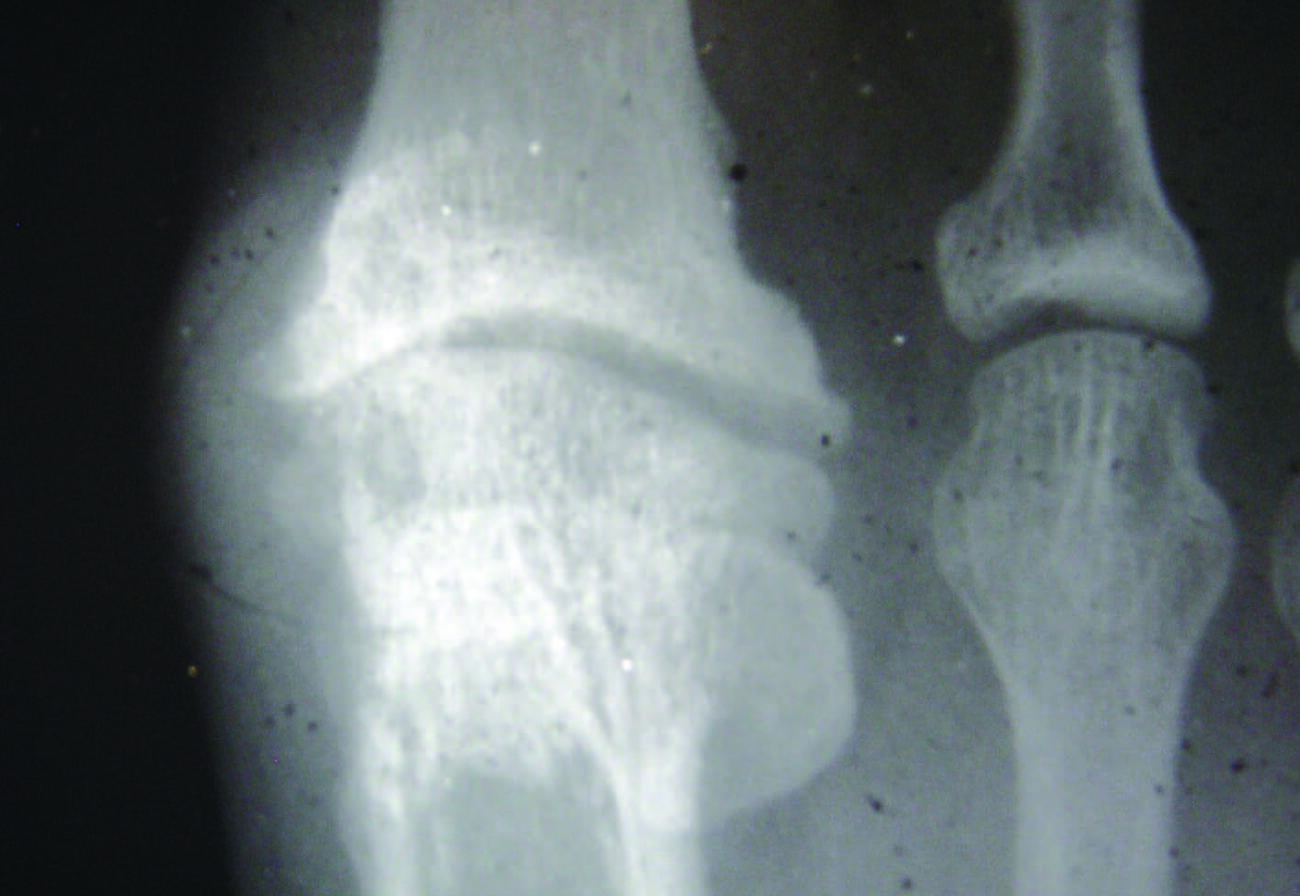

Stage 2. In stage 2, there is more dramatic loss in dorsiflexion at the first MPJ with only 10 to 30 degrees of dorsiflexion remaining, which can make ambulation difficult as well as painful.17 Radiographically, a more extensive dorsal osteophyte will be seen than in stage 1, with further decrease in the joint space. This stage now represents a structural hallux limitus.

Stage 3. In stage 3, the patient has lost nearly all motion in the first MPJ, now with less than 10 degrees of dorsiflexion remaining, and movement of the joint to the end range of motion causes the patient significant pain.17 Radiographically, there will be significant joint space narrowing, joint destruction, and with possible sesamoid change. This stage by definition constitutes a hallux rigidus.

Radiographic findings may be subtle or negative in the early phases of the condition.18 As the condition progresses, radiographic findings may reveal joint narrowing, thinning of articular surfaces, osteophytic changes of the base of the proximal phalanx, spurring of the metatarsal head, and possible fracture fragments/loose bodies. If previous injury to the sesamoids occurred, there may be degenerative changes there as well.18